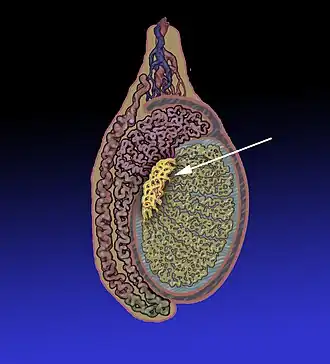

![]() Position of the rete testis within the testicle | |

![]() 1: Testicular septa 2: Convoluted seminiferous tubules 3: Testicular lobules 4: Straight seminiferous tubules 5: Efferent ductules 6: Rete testis | |